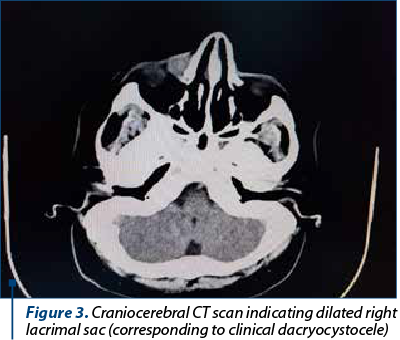

The therapeutic principles in nasolacrimal canal (NLC) stenosis are instrumental dilation, NLC stenting, endoscopic dacryocystorhinostomy (DCRS), external DCRS, and dacryocystectomy(5). The approaches are ophthalmic, ENT, and mixed. Before a therapeutic decision, it is essential to investigate using imaging by contrastography, which can objectify the obstruction of drainage through the nasolacrimal canal and the retention of the contrast substance in the tear sac(6) (Figure 2). Craniocerebral CT/orbit investigation provides additional data on nasal pathology and can be extremely useful before a radical surgical solution such as dacryocystectomy(7) (Figure 3).

Figure 3. Craniocerebral CT scan indicating dilated right lacrimal sac (corresponding to clinical dacryocystocele)